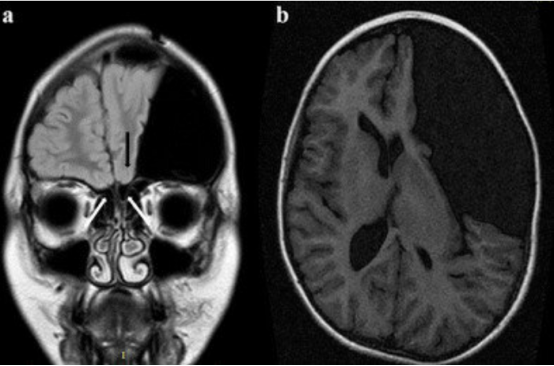

一名 11 歲男孩表現(xiàn)出 KS 的典型特征以及與外側(cè)裂蛛網(wǎng)膜囊腫相關(guān)的癥狀。因頭痛加重入院。入院時(shí),體檢顯示呈閹人外貌、小陰莖、既往有隱睪癥和嗅覺缺失。MRI 顯示左側(cè)外側(cè)裂蛛網(wǎng)膜囊腫較大,嗅球 / 嗅束復(fù)合體缺失,左側(cè)嗅溝發(fā)育不全?;純航邮芰藘?nèi)鏡下囊腫造瘺術(shù),隨后因硬膜下積液進(jìn)行了暫時(shí)性外部引流,并因囊腫復(fù)發(fā)進(jìn)行了顯微鏡下造瘺術(shù)。其身材生長正常,盡管進(jìn)行了激素替代治療,性發(fā)育仍延遲。

示例病例的術(shù)前 MRI(冠狀面)顯示嗅球缺失(白箭頭),左側(cè)嗅溝發(fā)育不全(黑箭頭)。左側(cè)眶回和右側(cè)回分化不良,部分被蛛網(wǎng)膜囊腫壓迫;b 注意左側(cè)較大的外側(cè)裂蛛網(wǎng)膜囊腫(術(shù)前 MRI 軸面)。